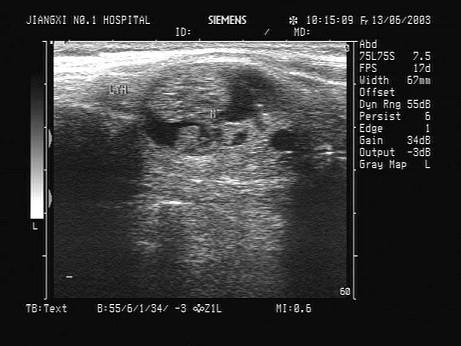

问题 患者发现颈部肿块数年,无明显不适。甲状腺超声如图,最可能的诊断为?(?)

选项 A.甲状腺癌 B.结节性甲状腺肿 C.甲状腺炎 D.甲状腺腺瘤并囊变 E.甲状腺囊肿

答案 D